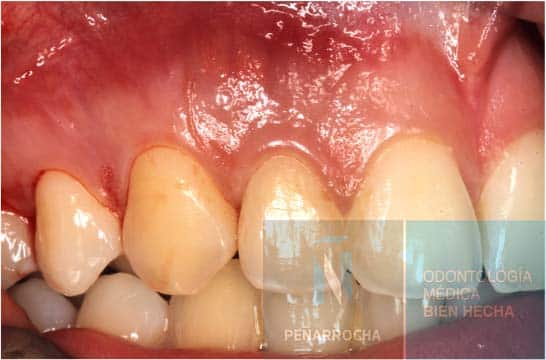

Swelling of the Gum or Affected Area

Inflammation around the treated tooth can appear as localized swelling in the gums and, in some cases, as visible swelling in the face. The extent of the infection and the location of the tooth determine how severe the swelling may become.

If left untreated, the infection may progress into an acute periapical abscess, with pus formation, increased pain, and even general malaise. In such cases, immediate consultation with an endodontist is essential.

Fistulas or Pus Discharge

Fistulas appear as small whitish bumps near the affected tooth. They act as drainage points for pus caused by infection. Although they may not always be painful, fistulas are a sign of an active infection inside the tooth.

These lesions may come and go intermittently. Without proper treatment, the infection can spread to the surrounding bone or soft tissues. A clinical exam combined with X-rays or CBCT imaging is needed for a definitive diagnosis.